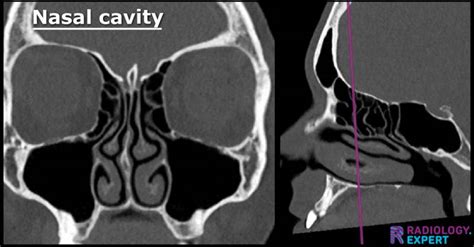

If you have been suffering from persistent sinus pressure, chronic congestion, or mysterious facial pain, your healthcare provider may recommend a Nasal CT scan to get a clearer picture of what is happening inside your nasal passages. This specialized imaging procedure is a cornerstone of modern otolaryngology, providing doctors with high-resolution, three-dimensional views of the complex structures within your nose and paranasal sinuses. Unlike a standard X-ray, which offers a two-dimensional look, a computed tomography (CT) scan provides detailed cross-sectional images, allowing specialists to pinpoint inflammation, structural abnormalities, or obstructions with remarkable accuracy.

A Nasal CT scan, often referred to as a sinus CT scan, is a non-invasive diagnostic tool that uses X-ray technology paired with advanced computer processing to create detailed images of your sinus cavities and nasal anatomy. When you undergo this scan, you will lie on a table that slides into a doughnut-shaped machine. The scanner rotates around your head, capturing multiple images from different angles to construct a comprehensive view of the area.

The primary purpose of this imaging is to assist ear, nose, and throat (ENT) specialists in diagnosing conditions that cannot be easily visualized during a routine physical examination. Because the sinuses are deep within the skull, traditional physical inspections only show a small portion of the nasal cavity. A CT scan, however, reveals the entire network of sinuses, highlighting potential issues that may require medical or surgical intervention.

Once the images are captured, a radiologist will review them and generate a report. They look for specific markers of health, such as clear, air-filled sinus cavities, versus signs of pathology, such as fluid accumulation, mucosal thickening, or bone erosion. Your ENT specialist will then combine these results with your clinical symptoms to make a definitive diagnosis.